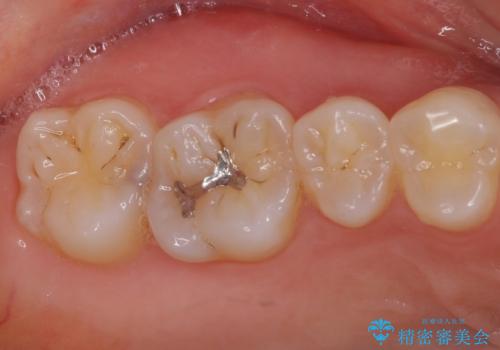

セラミックとゴールド 奥歯のむし歯治療

- 奥歯の銀歯と虫歯を気にして来院された患者様です。

下顎は口を開けたときに目立つためセラミックインレーに、上顎奥歯は機能面を優先してゴールドインレーにて修復治療を行うこととしました。

機能面を優先すると、PGAインレー(ゴールドインレー)による修復治療やPGAクラウンによる補綴治療が望ましいのですが、笑ったときに見えている銀歯がどうしても気なってしまうとのことで、目立ってしまう奥歯はセラミックインレーやセラミッククラウンを装着することとしました。